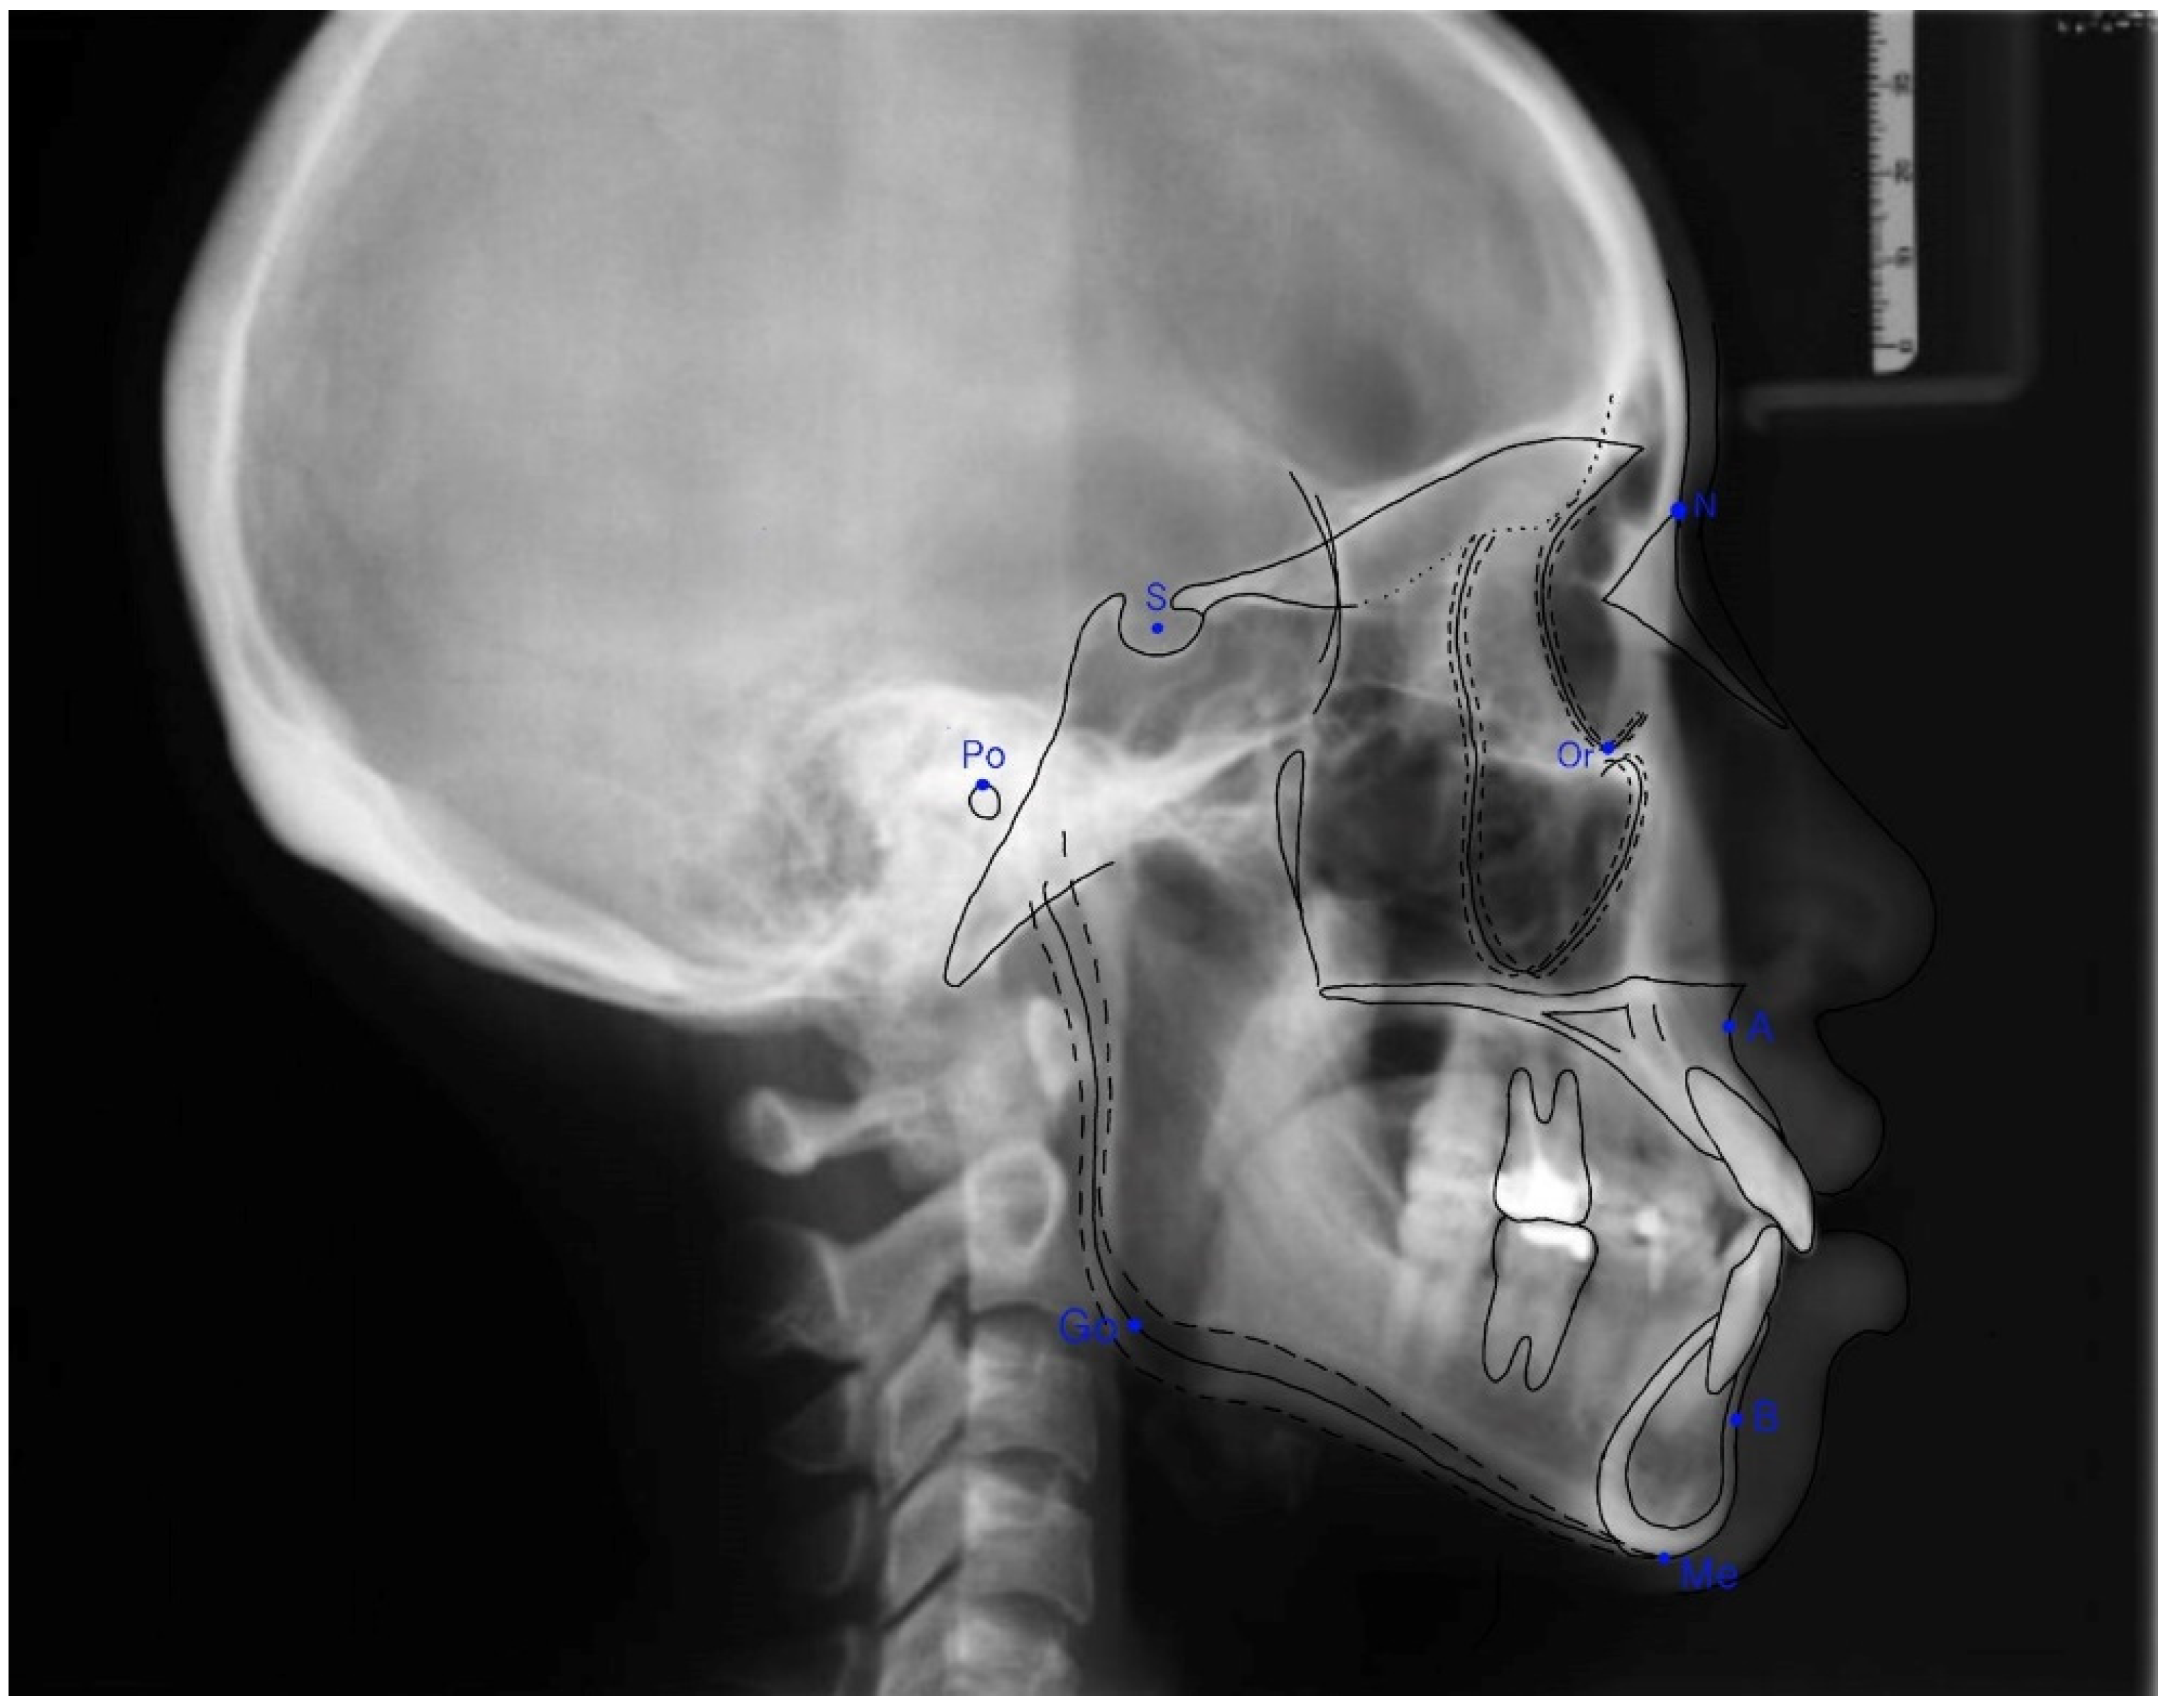

2.3. Assessment of the Sagittal Skeletal Relationship

The anterior-posterior skeletal relationship between the maxilla and the mandible of the orthodontic patient was classified as Class I, Class II, or Class III (Figure 1 and Figure 2) according to Steiner’s [8] and Tweed’s [9] analyses (Table 1).

Figure 1. The landmarks used to analyze lateral cephalometric radiographs.

Table 1. Definitions of terms used in assessing the sagittal skeletal relationship.

LandmarkDefinition

Sella (S)The center of the hypophyseal fossa (sella turcica)

Nasion (N)The junction of the nasal and frontal bones at the most posterior point on the curvature of the bridge of the nose

Porion (Po)The uppermost point of the external ear meatus

Orbitale (Or)A point midway between the lowest point on the inferior margin of the two orbits

Menton (Me)The lowest point on the symphysis of the mandible

A point (A)The innermost curvature of the maxillary apical base

B point (B)The innermost curvature from the chin to the alveolar junction